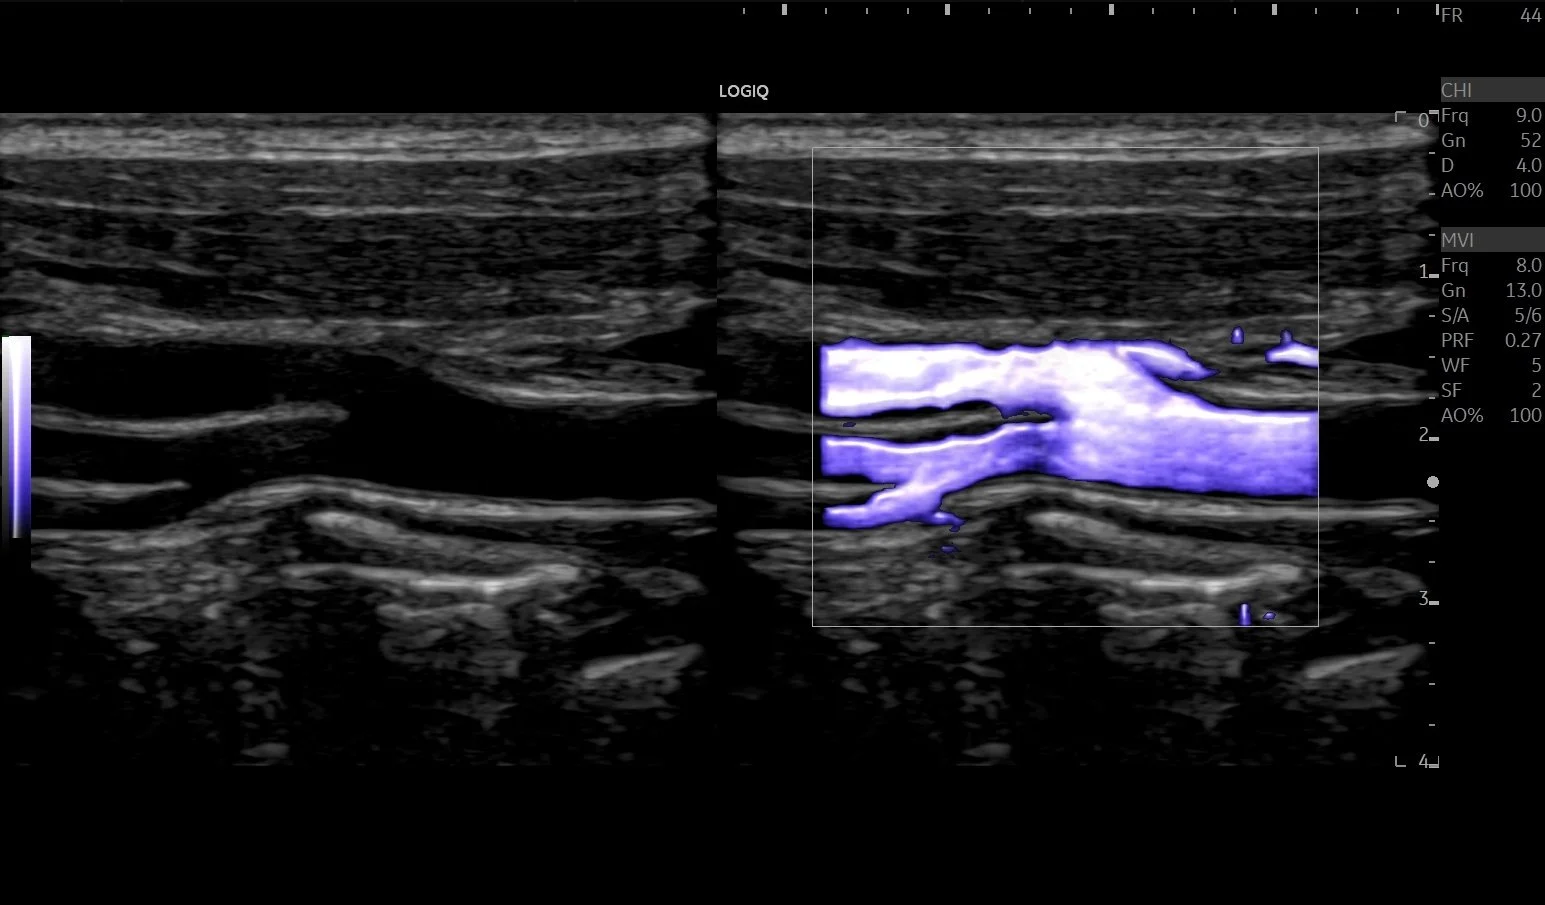

Doppler and vascular ultrasound focus on blood flow and blood vessels. This technique can detect blockages, narrowing, or abnormalities in arteries and veins, helping diagnose circulatory issues and guide treatment.

Doppler/Vascular

Arterial Lower/Upper Limb

Deep Vein Thrombosis (DVT) Upper/Lower Limb

Chronic Venous Insufficiency (CVI)

Carotids

Renal Doppler

Aorta Doppler